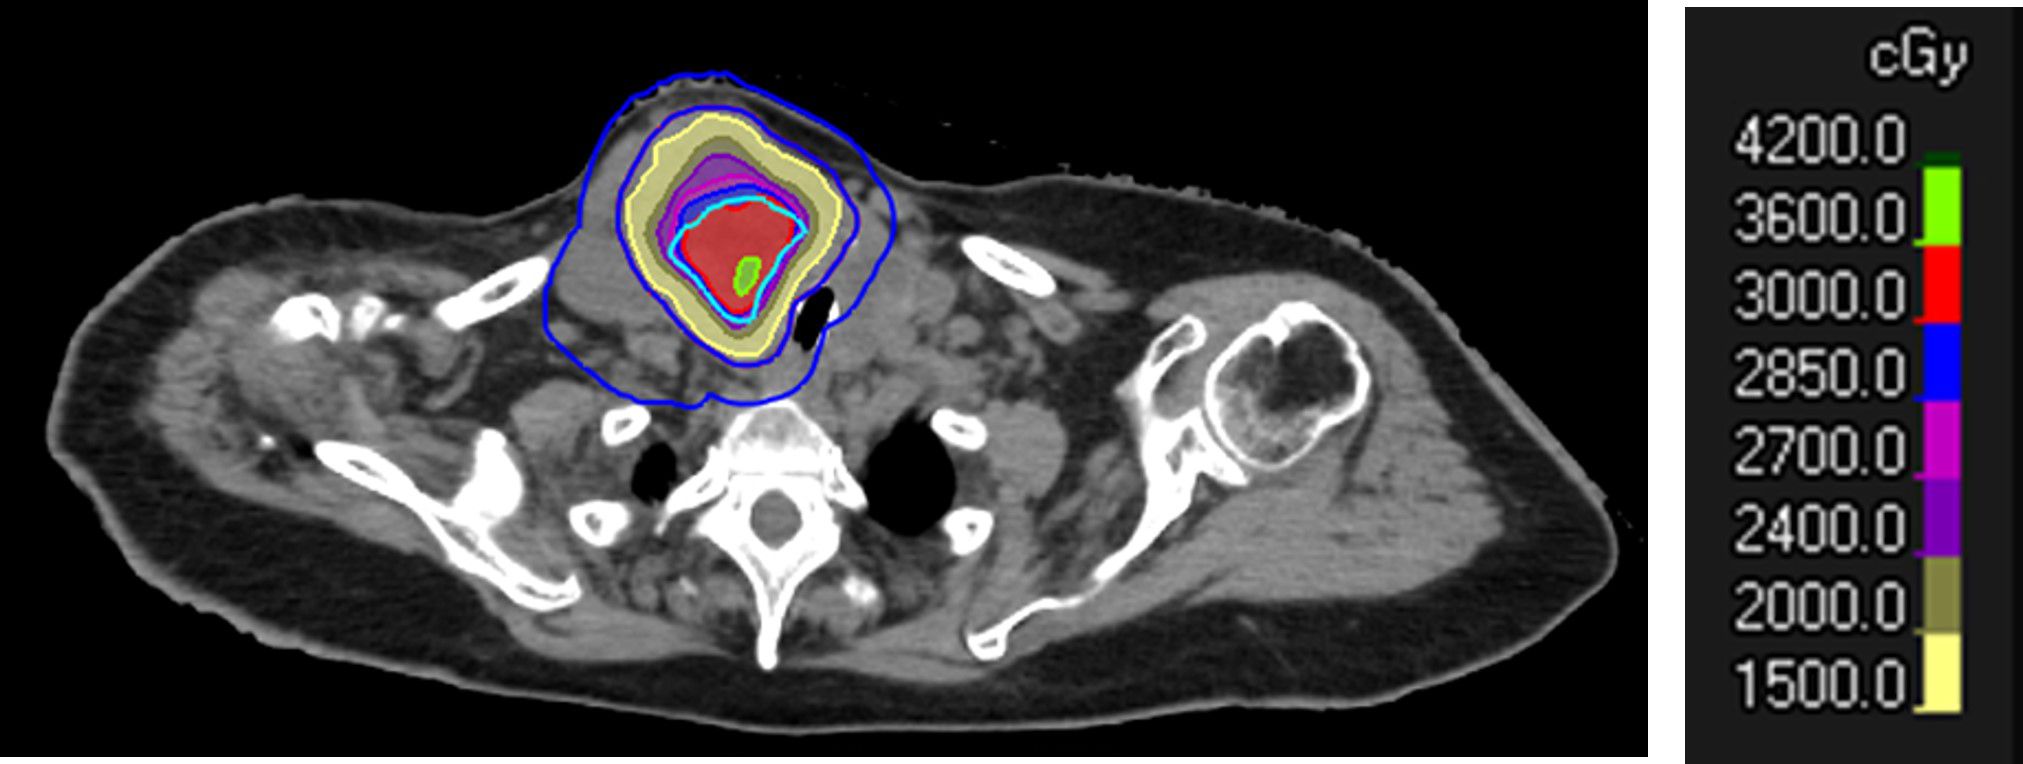

Early Experience with SBRT-based Partial Tumor irradiation targeting Hypoxic segment (SBRT-PATHY) of large bulky tumors.

Large bulky tumors possess poor prognostic characteristics that make tumor control difficult. SBRT-based Partial Tumor irradiation targeting Hypoxic segment (SBRT-PATHY) has been described as a spatially fractionated radiotherapy technique that induces both bystander and abscopal effects by sparing the peri-tumoral immune micro-environment thus minimizing the negative effects of radiation induced lymphopenia. The aim of these case reports is to present our early experience of 4 cases in the utilization of SBRT-PATHY at our institution.